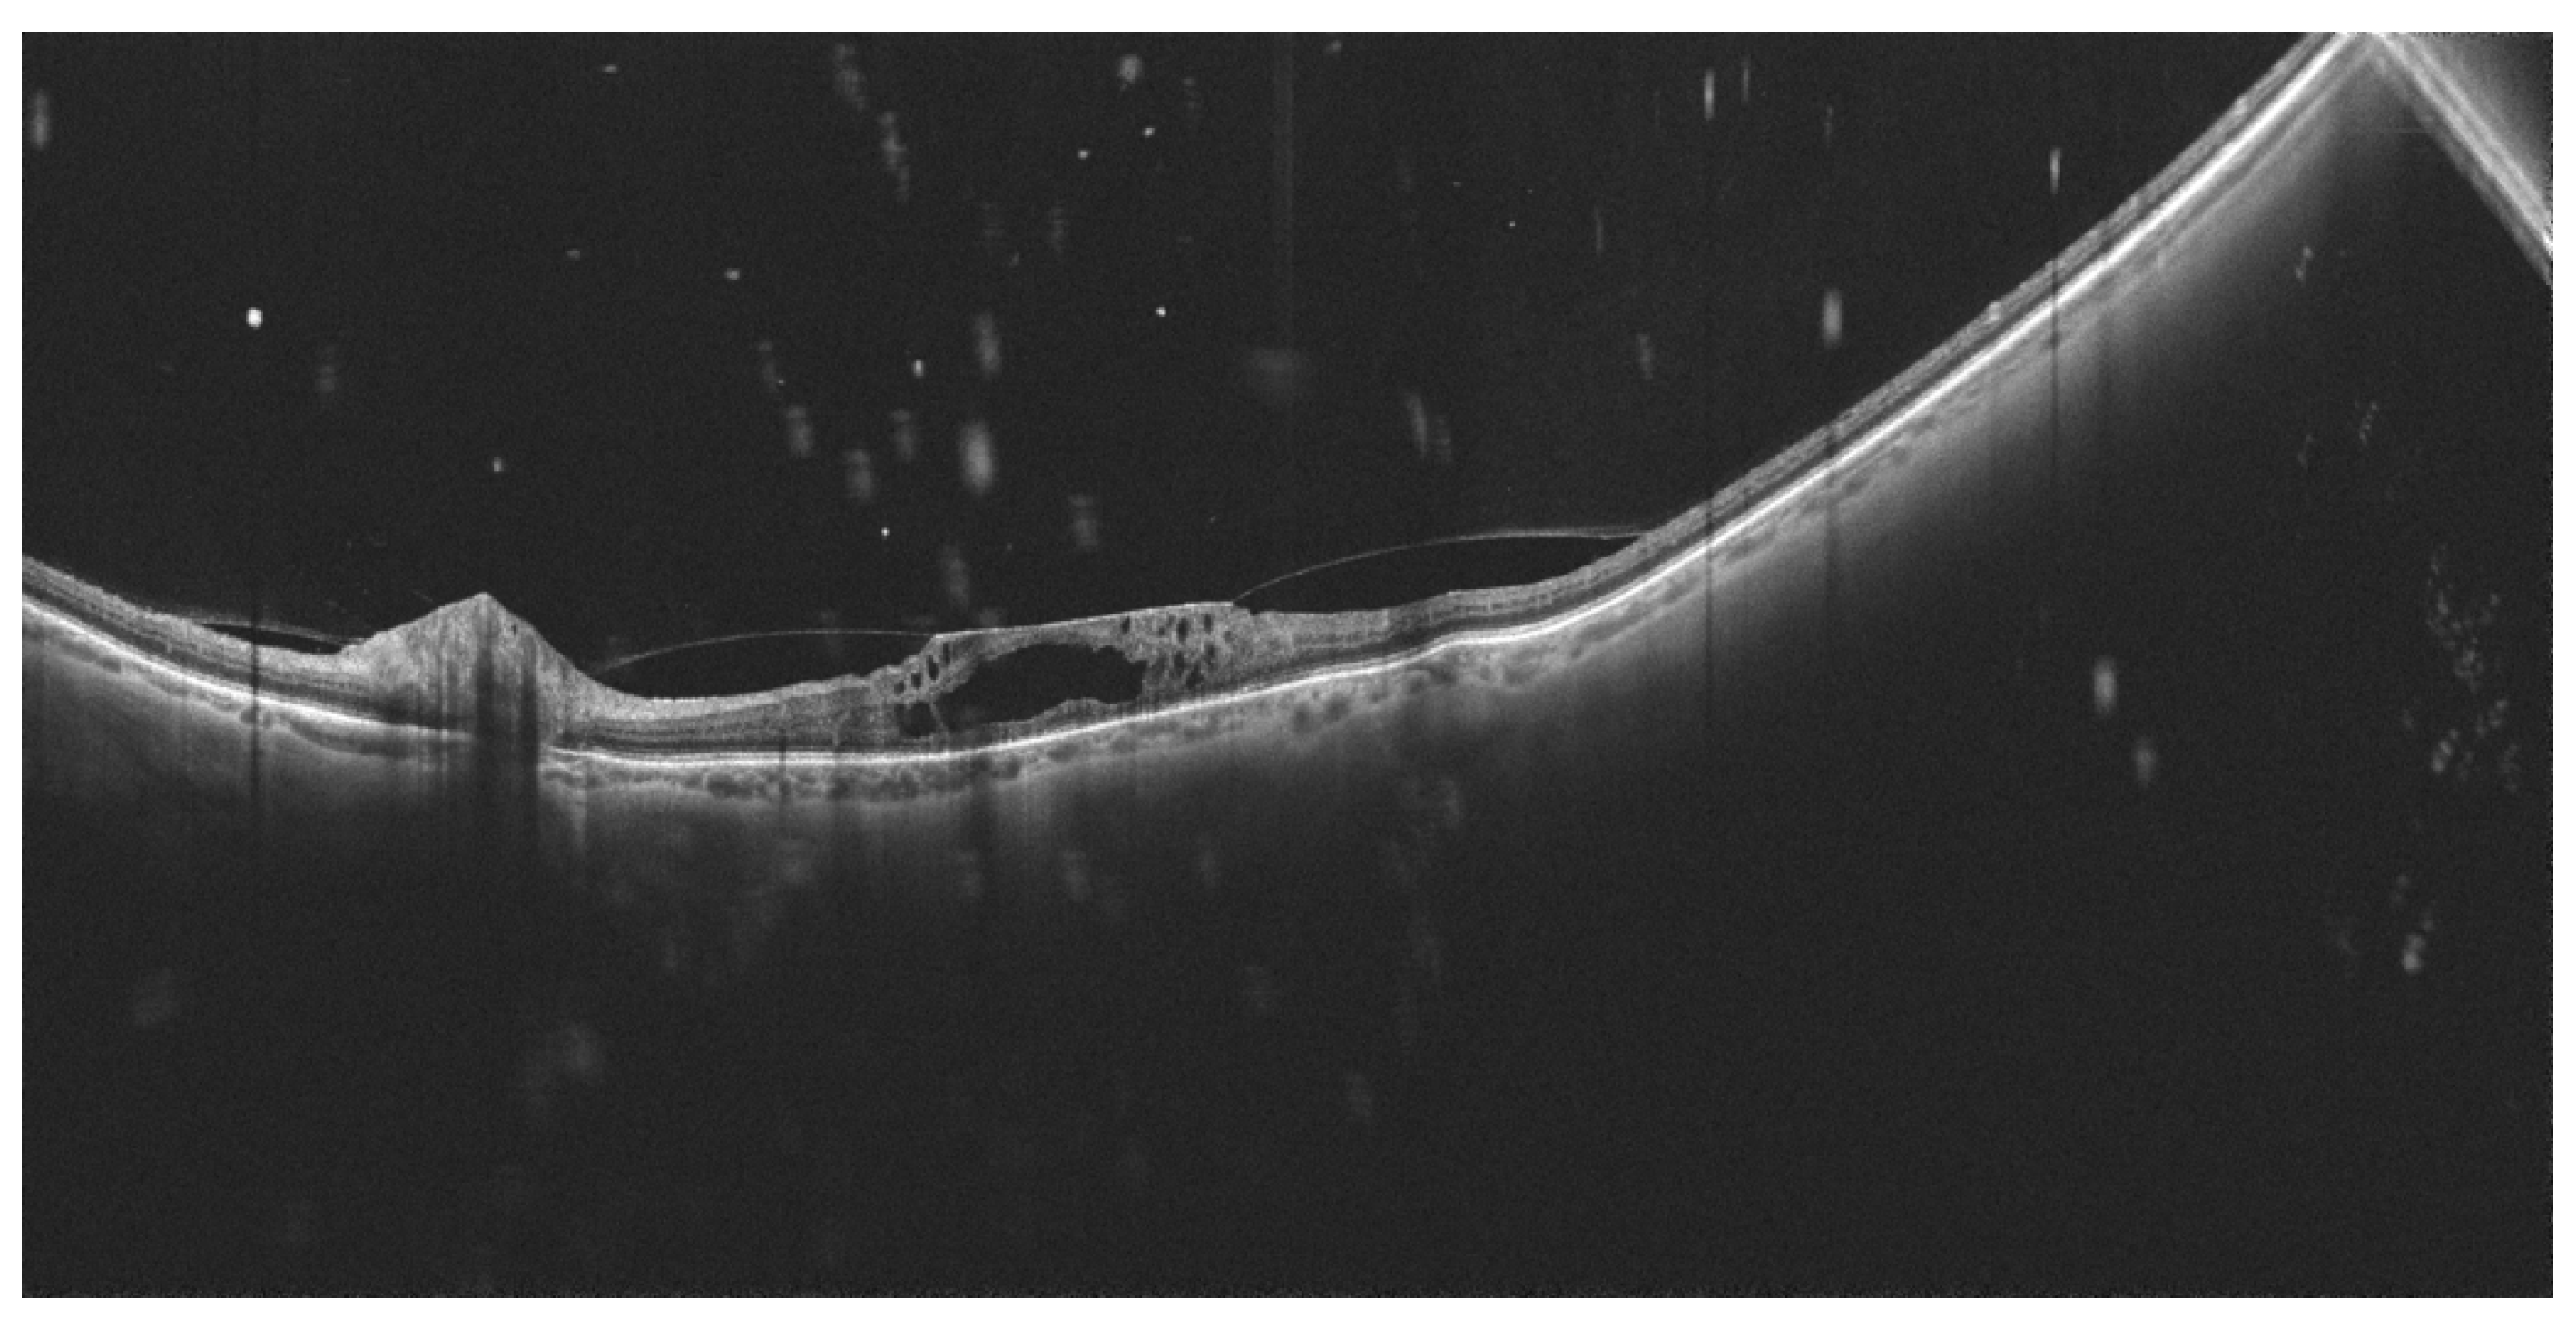

- Govetto, A.; Sebag, J.; Lucchini, S.; Ballabio, C.; Matteucci, M.; Ranno, S.; Carini, E.; Virgili, G.; Bacherini, D.; Radice, P. Imaging rhegmatogenous retinal lesions and peripheral vitreo-retinal interface with wide-field optical coherence tomography. Retina 2023, 44, 269–279. [Google Scholar] [CrossRef] [PubMed]

- Kurobe, R.; Hirano, Y.; Ogura, S.; Yasukawa, T.; Ogura, Y. Ultra-Widefield Swept-Source Optical Coherence Tomography Findings of Peripheral Retinal Degenerations and Breaks. Clin. Ophthalmol. 2021, 15, 4739–4745. [Google Scholar] [CrossRef] [PubMed]

- Zhang, T.; Wang, Z.; Sun, L.; Li, S.; Huang, L.; Liu, C.; Chen, C.; Luo, X.; Yu, B.; Ding, X. Ultra-wide-field scanning laser ophthalmoscopy and optical coherence tomography in FEVR: Findings and its diagnostic ability. Br. J. Ophthalmol. 2021, 105, 995–1001. [Google Scholar] [CrossRef] [PubMed]

- Wang, Y.; Lai, Y.; Zhou, X.; Zhang, T.; Sun, L.; Zhang, Z.; Huang, L.; Li, S.; Ding, X. Ultra-wide-field optical coherence tomography angiography in mild familial exudative vitreoretinopathy. Retina 2023, 43, 932–939. [Google Scholar] [CrossRef]